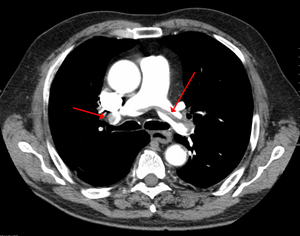

SaddlePE.PNG

Chest spiral CT scan with radiocontrast agent showing multiple filling defects both at the bifurcation ("saddle" pulmonary embolism) and in the pulmonary arteries